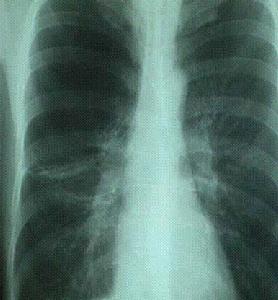

胸部X線檢查常規拍攝後前位片,有時則需加攝側位片。X線胸片可良好地顯示心臟和大血管的輪廓,肺臟嚴重疾病,以及鄰近的腔隙和包括肋骨在內的胸廓情況。例如,X線胸片可清晰地反映肺炎、肺腫瘤、氣胸、胸腔積液和肺氣腫等病變。儘管X線胸片不能提供胸部病變的確切原因,但有助於醫師選擇具有確診價值的檢查方法。

與X線胸片相比,胸部計算機體層攝影(CT)掃描更能顯示病變的詳細情況。CT掃描時,計算機可對一系列X線影像進行分析,然後提供數個橫斷面影像。CT掃描過程中,可口服或經血管注入染料,以使一些胸部病變顯示更加清楚。